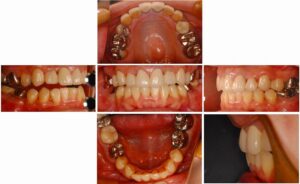

今日、ワイヤーでの矯正患者様が、三年の治療を経て、はれて終了しました。お疲れ様でした。 この方は、舌側矯正と言って、裏側に矯正装置を付ける方法を選択されたので、他人からは矯正の装置が見えず、治療していると気付かれません。 テクニックも複雑で […] 本文を読む